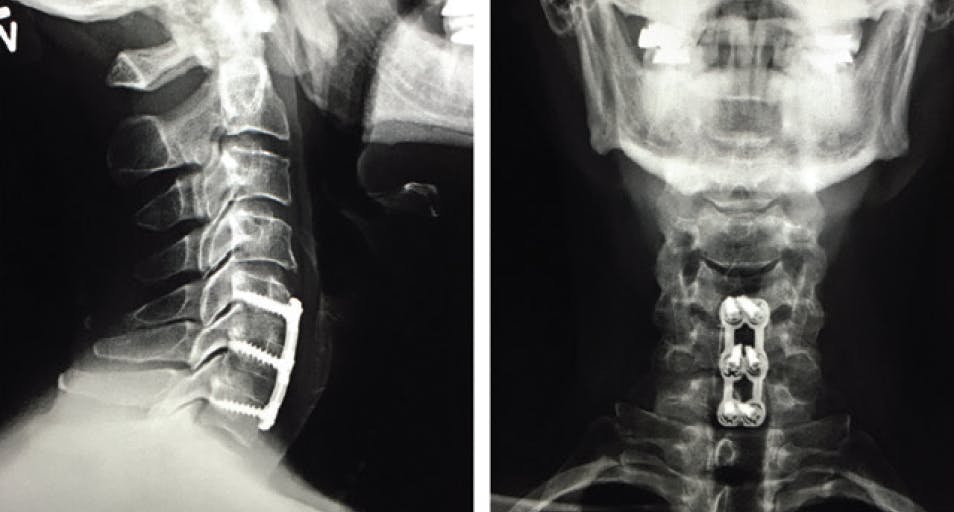

In 2015, I slipped on a puddle of water on the OR floor and fell. I subsequently developed a large L5-S1 disc herniation (Figure 1) that caused severe back pain and progressive weakness in my right leg that prevented me from working or traveling. I saw two neurosurgeons and one orthopedic surgeon, all of whom were ready to operate, but I was not ready to undergo surgery.

Figure 1. An MRI of Dr. Dhaliwal’s spine in December 2015 showing an L5-S1 disc herniation (red circle).

My outcome was excellent, and because I am healthy and fit I was able to achieve fusion much faster than most people do (Figure 5). I was also fortunate to have one of the world’s best cervical spine surgeons perform my surgery. Not everybody is so lucky, and not all spinal fusion surgery outcomes are so positive. A far better situation is never to require surgery for an occupationally associated MSD; thus, I strongly recommend taking steps to optimize ergonomics and posture in the clinic and OR to avoid these occupational strain injuries that can lead to permanent nerve damage.